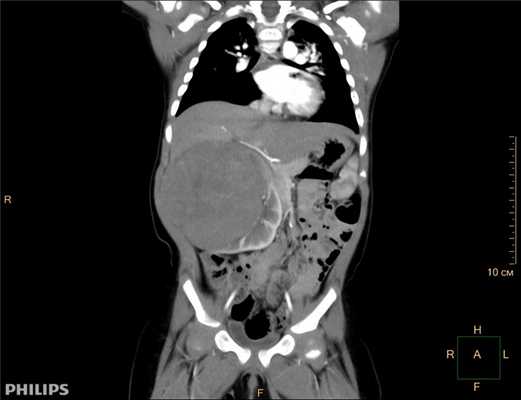

Компьютерная томография более детально дает информацию об анатомическом отношении опухоли к окружающим тканям и органам, позволяет оценить структуру опухоли (рис. 5).

Рис. 5. КТ нейрогенного образования забрюшинного пространства справа